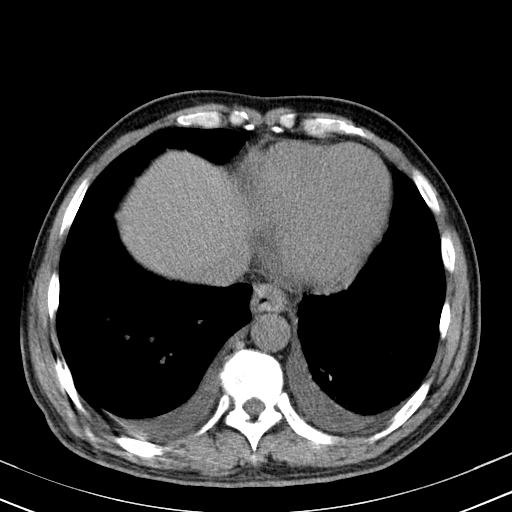

以下是引用zjzjr在2010-3-21 17:39:00的发言:[br]右下中心型肺癌并阻塞性肺炎/不张,纵膈淋巴结肿大,右侧大量胸腔积液,左侧少量胸腔积液

以下是引用zxl51642在2010-3-21 17:06:00的发言:[br]右下中心型肺癌并阻塞性肺炎/不张,纵膈淋巴结肿大,右侧大量胸腔积液,左侧少量胸腔积液,少量腹水。建议纤维支气管镜进一步检查。